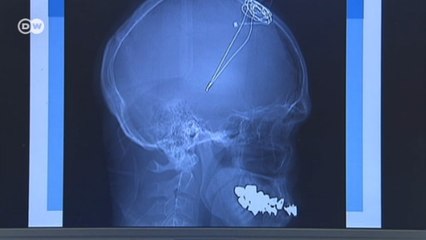

O neurologista Sergio Jordy participou do episódio desta semana do Jovem Pan Saúde para alertar para os diagnósticos da doença de Parkinson, ressaltando a importância de identificar os sintomas o mais rápido possível.